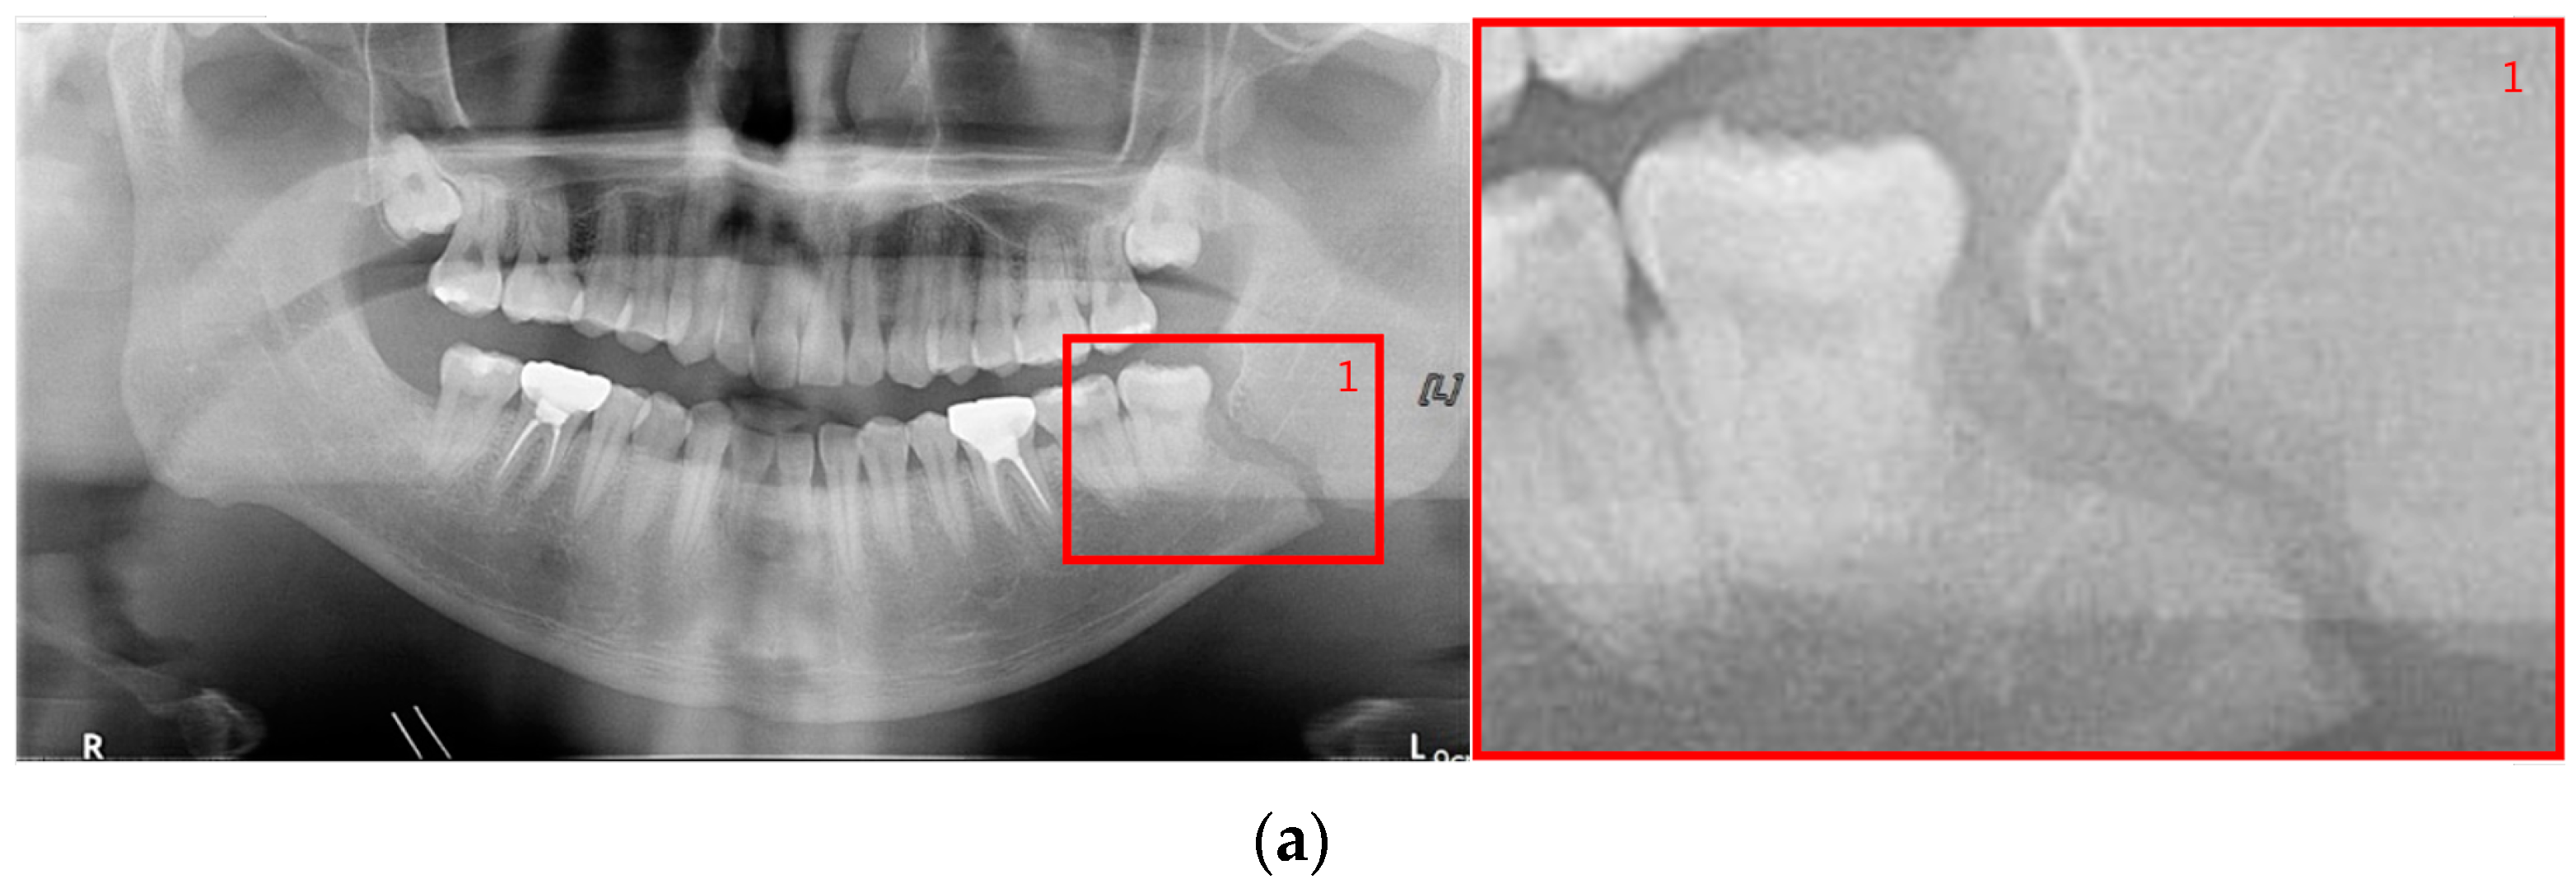

The shape of fractures in the panoramic radiographic image generally shows an oblique fracture with a gap and a shear fracture with a step in red boxes one and two (Figure 2). However, in the condyle region, the fracture shape differs from the general fracture shape, and the bones in the condyle region seem to overlap (dislocation) in red boxes 3 and 4 []. Owing to the similarity between the phenomenon that looks like a fracture due to the difference in shading on the panoramic radiographic image and the shape of a specific fracture, such as a fracture in the condyle region, the expert needs to make a careful judgment. Therefore, deep learning methods can help reduce physician errors and support medical diagnoses.

Figure 2.

The shapes of mandibular fractures: (a) oblique fracture on an angle area; (b) shear fracture and severe shear fracture on a symphysis area; and (c) displaced fracture on a condyle area.